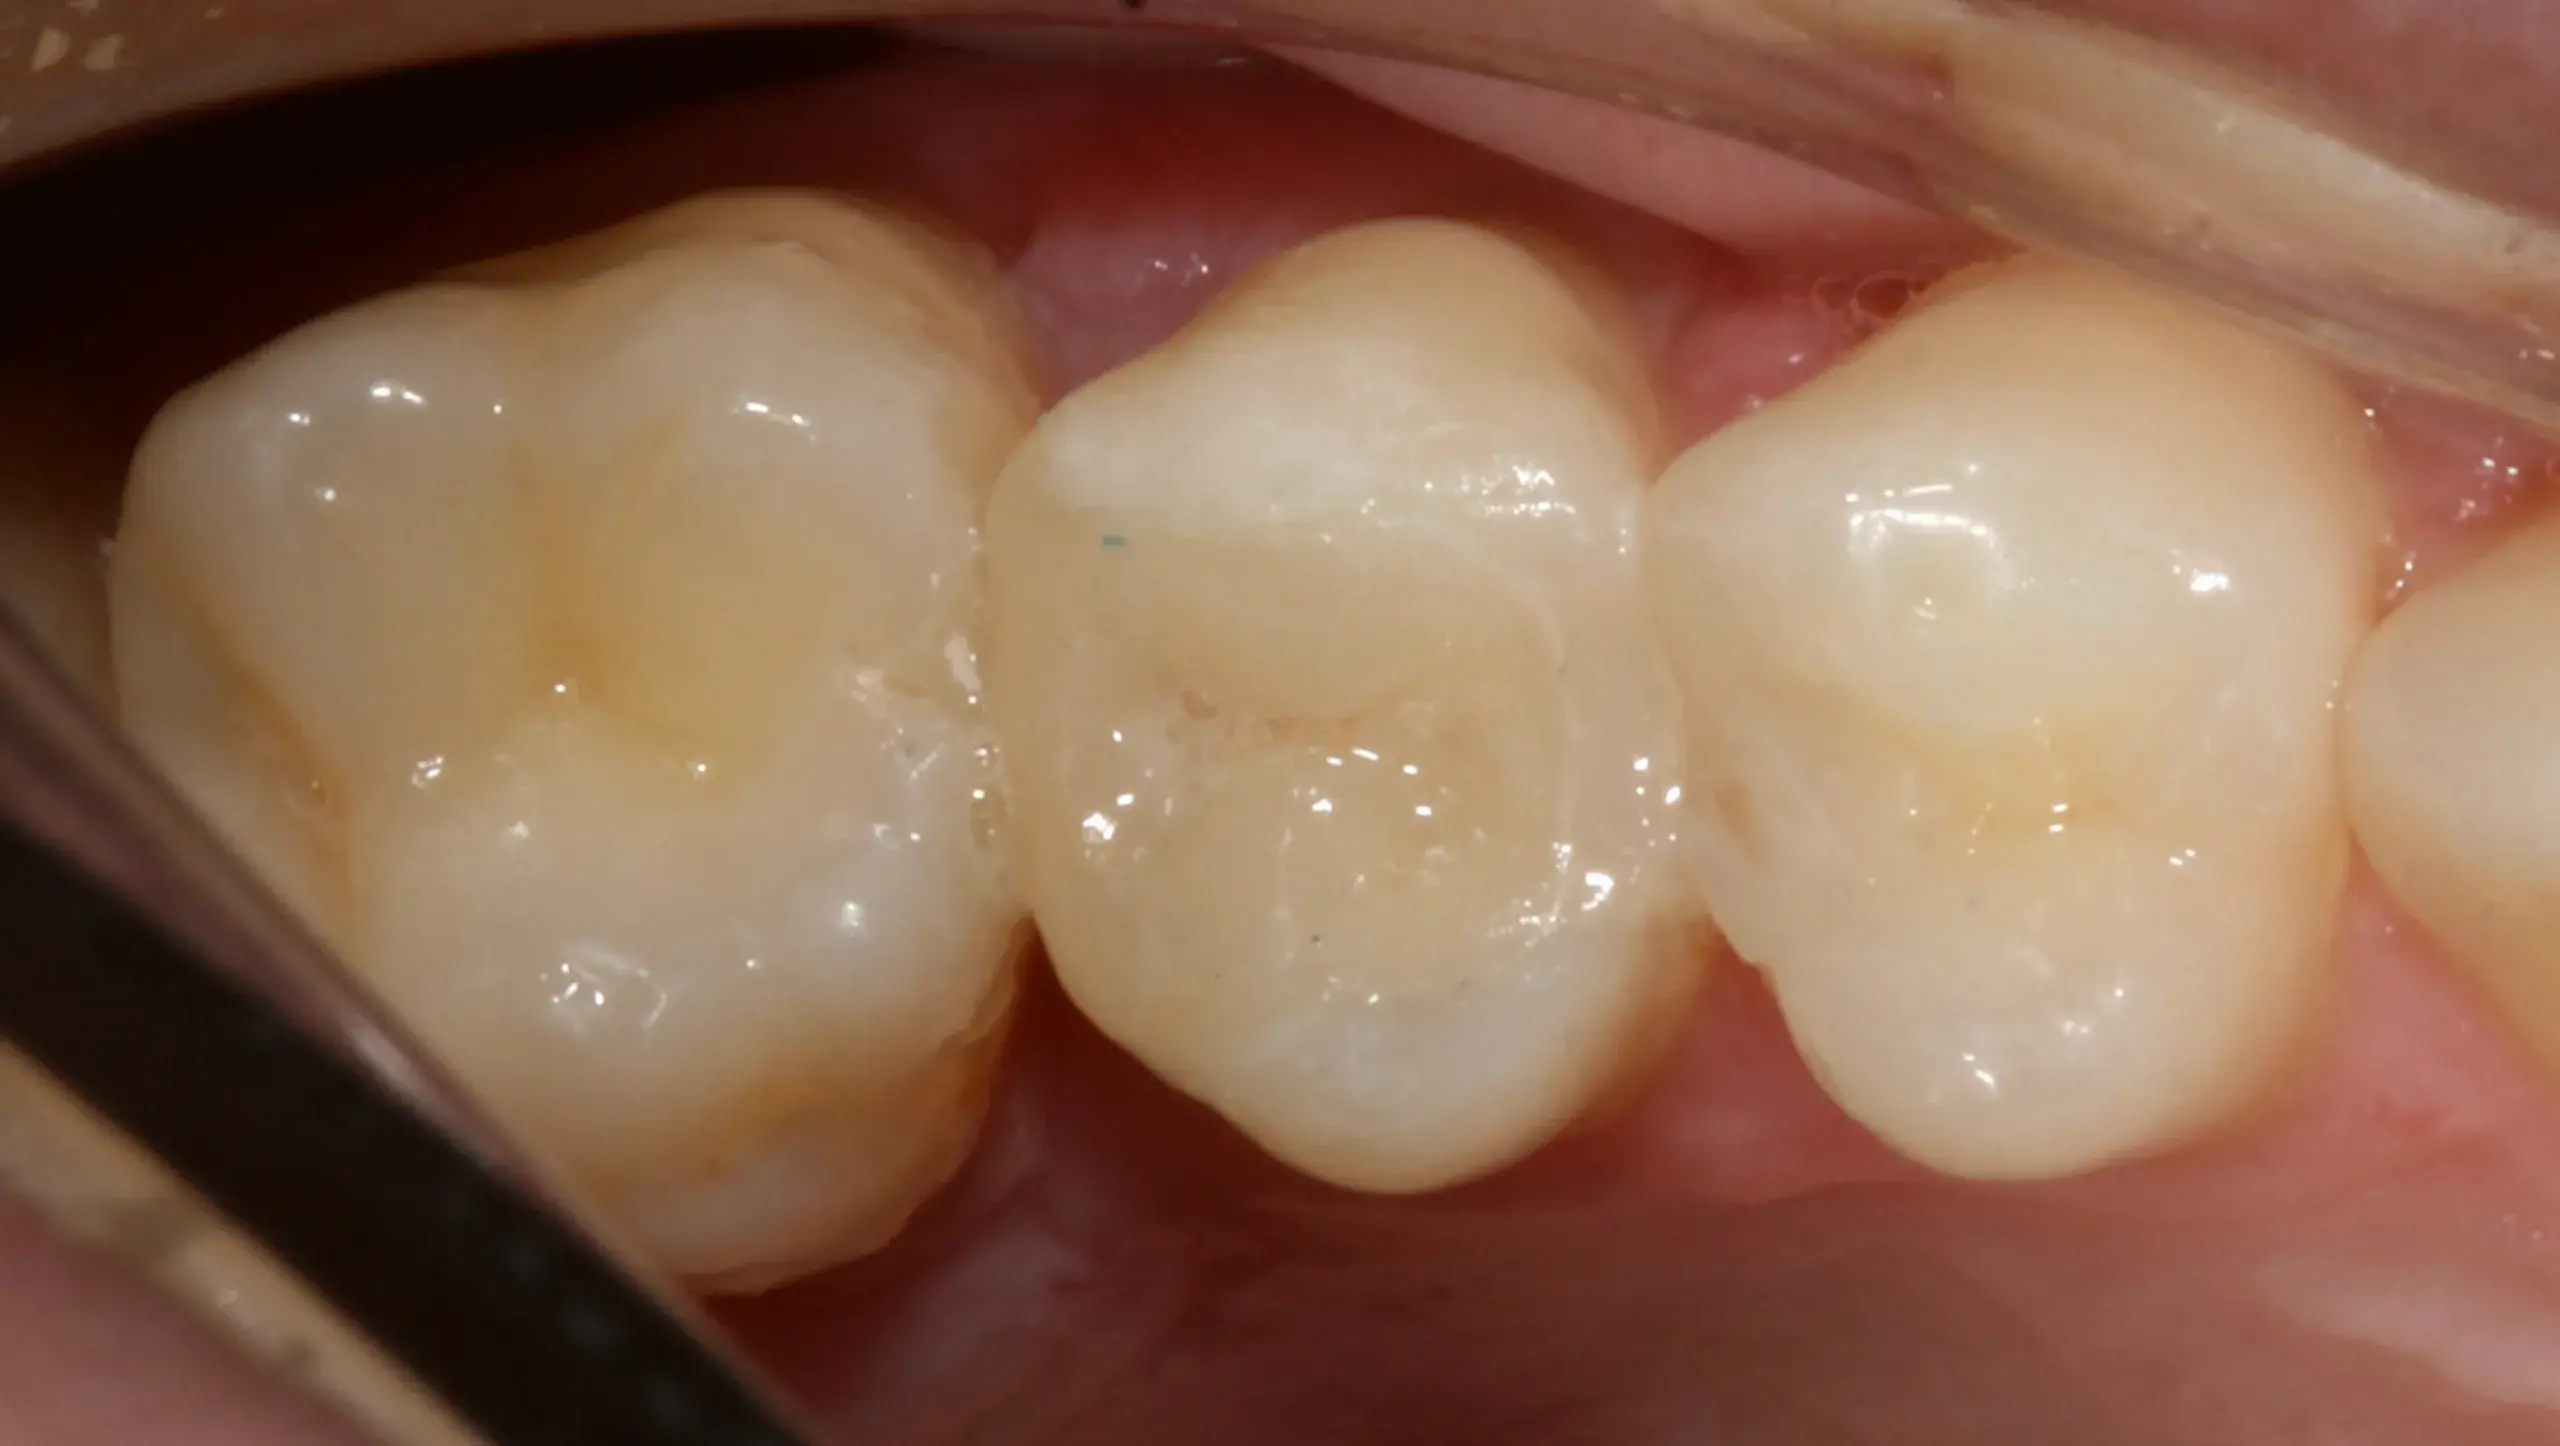

Caso clínico 9: Caries

Caso clínico 9: Caries En el siguiente caso clínico se puede observar un tratamiento de endodoncia microscópica de los dientes anteriores seguido de una restauración conservadora mediante incrustación de disilicato…